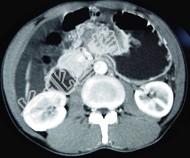

- 单项选择题男,65岁, 中上腹痛腹胀、消瘦、乏力、纳差,影像检查如图, 最可能的诊断是  (    )

- A、胃间质瘤

- B、萎缩性胃炎

- C、肥厚性胃炎

- D、胃窦癌

- E、胃淋巴瘤